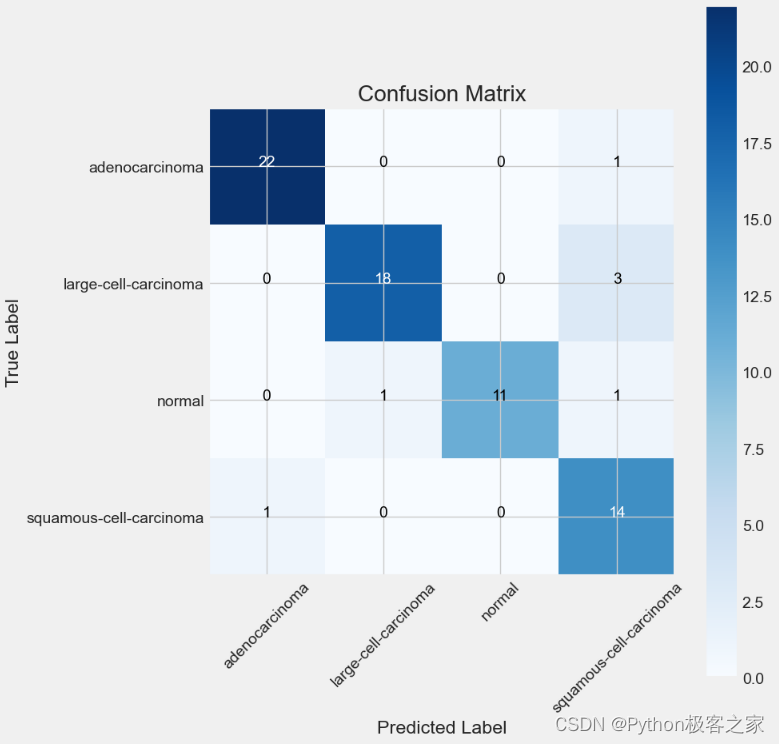

绘制模型性能评估结果的混淆矩阵:

5. 模型预测评估

利用训练集和验证集完成模型的训练和验证后,利用测试集进行预测评估,测试集预测准确率达到 90.28%